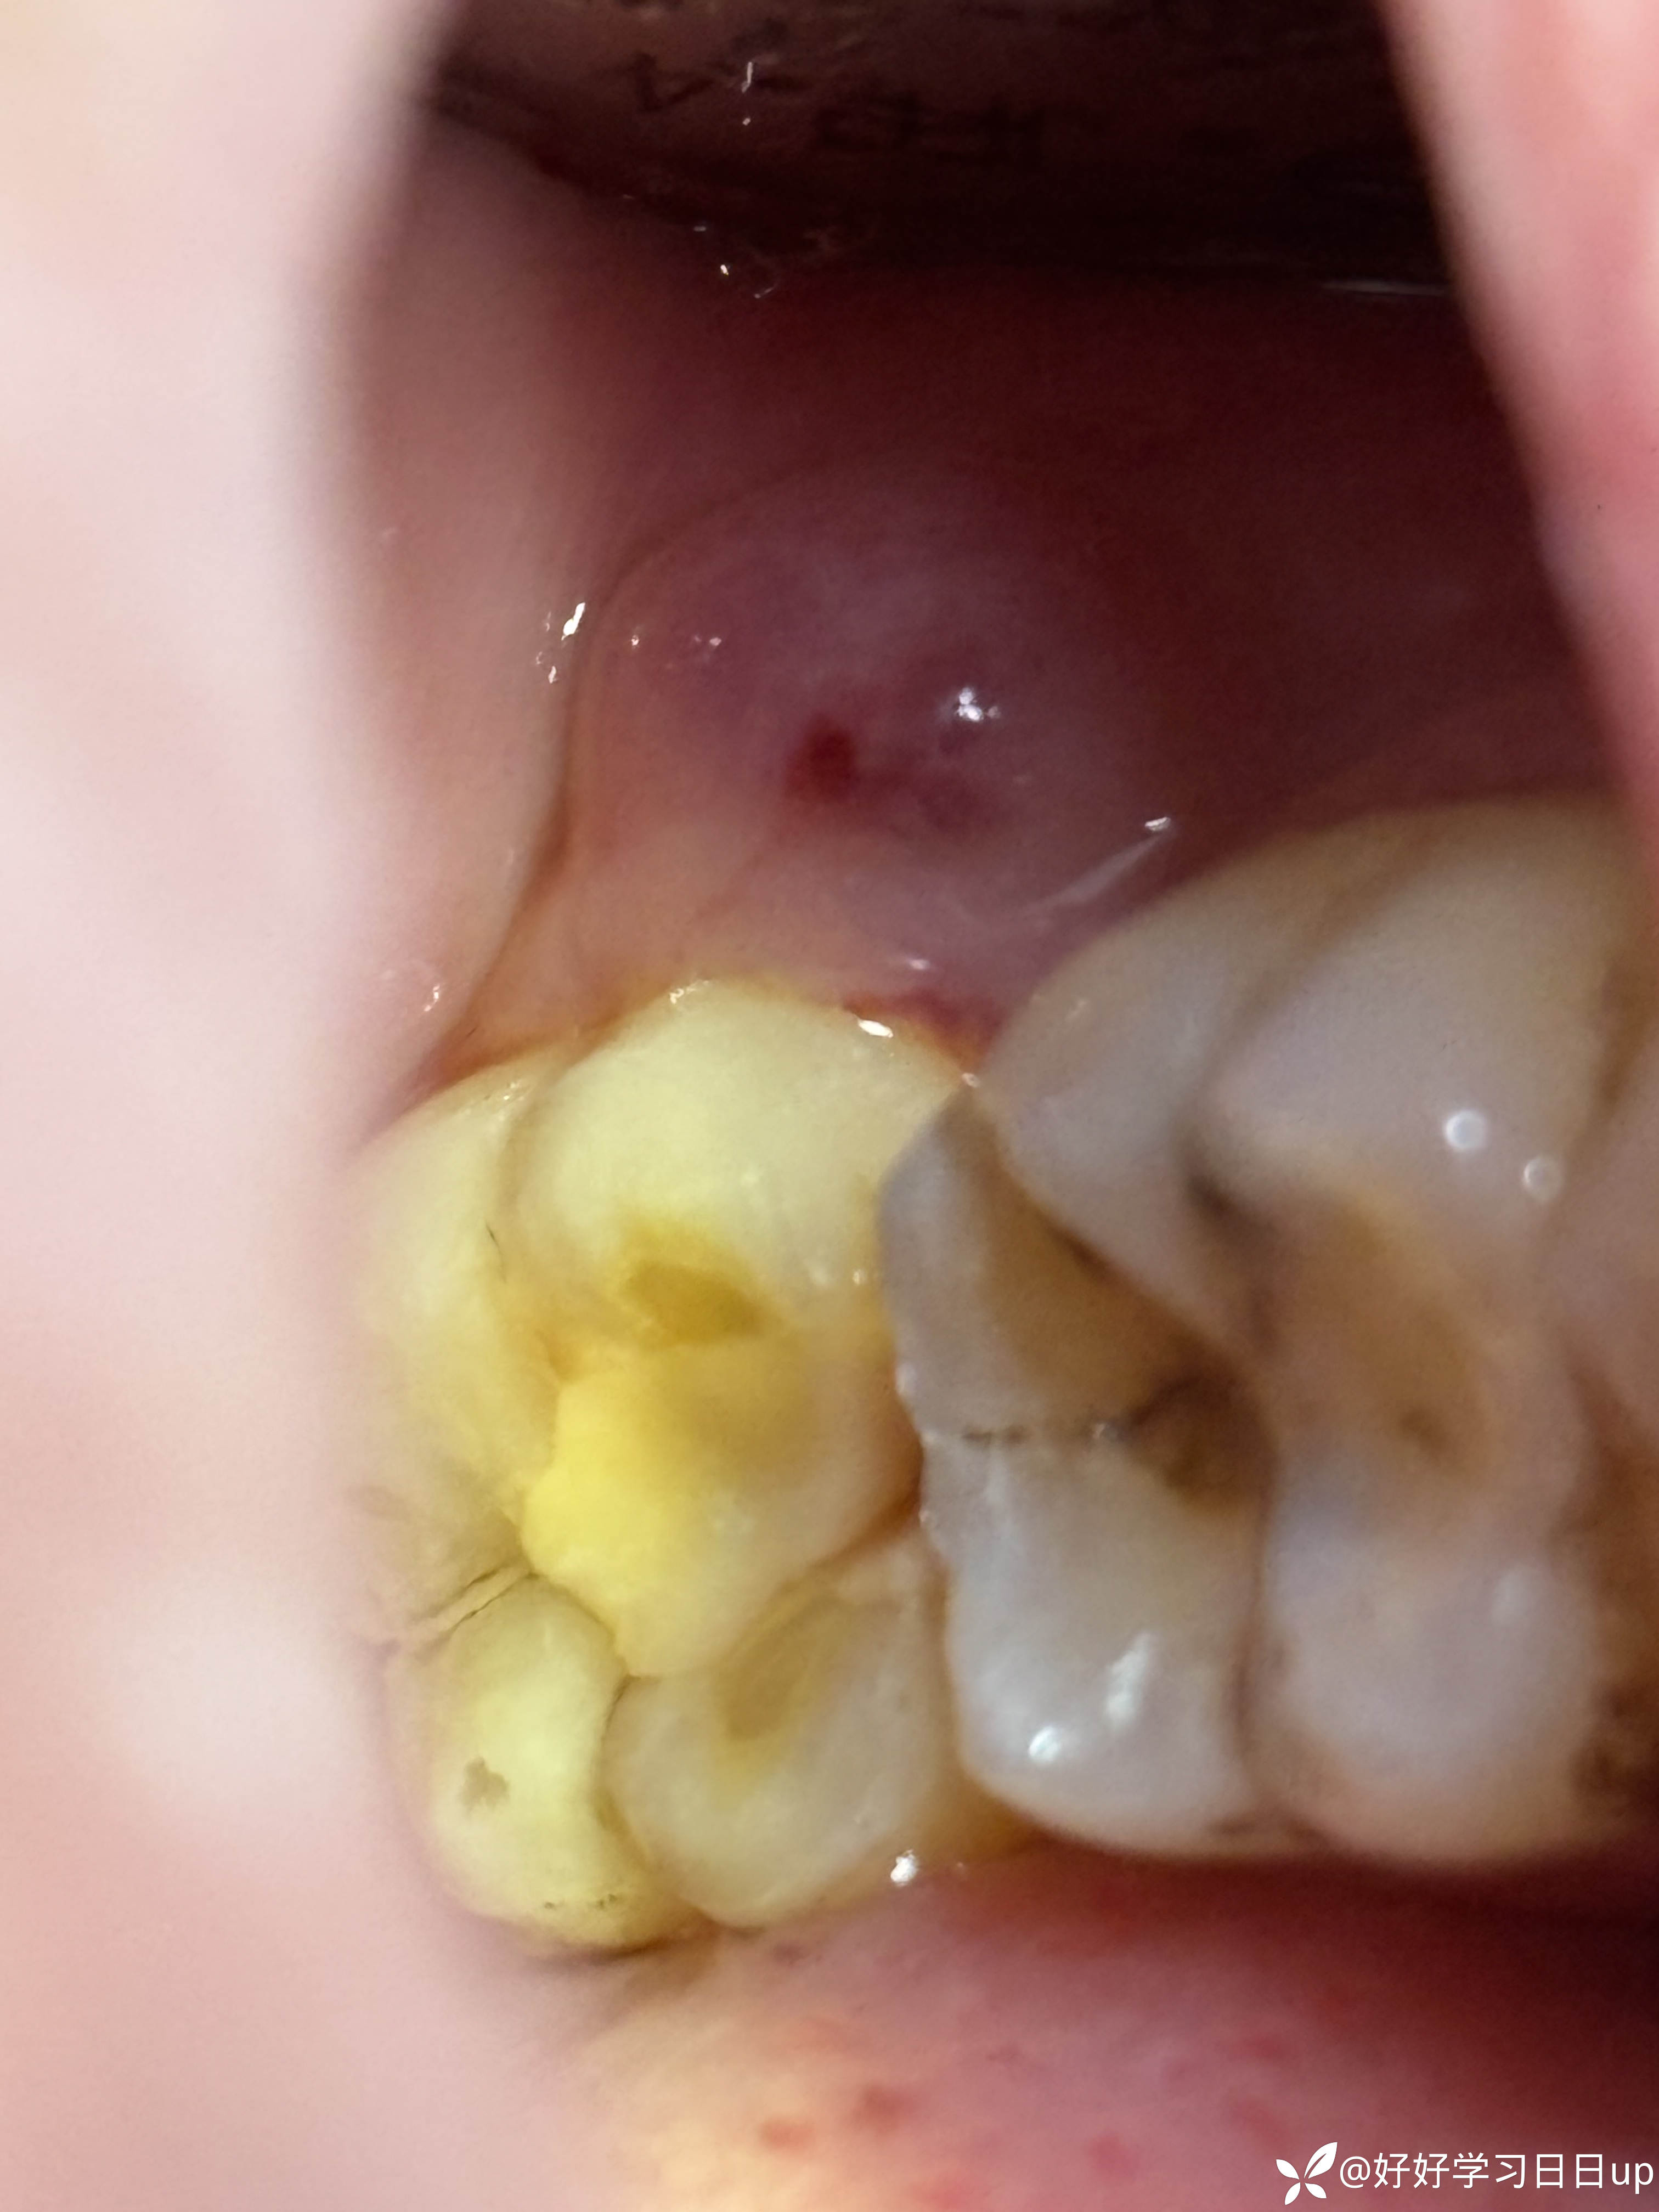

最近又来了几次还是塞牙的问题,患者自己想做冠,但是牙齿1度松动牙周较差,牙齿轻微扣痛,后方还有一颗埋伏度智齿,重新充填后龈上洁治后嘱咐观察

今天来了说肿了补的位置牙线用的过程中掉了一块,口内看可能是牙周脓肿,于是拍了一张根尖片,感觉不是根管引起的瘘管,引流脓液,洁治后,发现近中缺损部位疑似隐裂,拆除充填体发现隐裂贯穿近远中但是裂的位置卡不进探针,再次向下打磨隐裂部位,本来想完全去除隐裂,但没想到裂的还是比较深害怕抗力越来越差,跟患者说可能需要拔除,或者降低咬合后续观察,患者选择降低